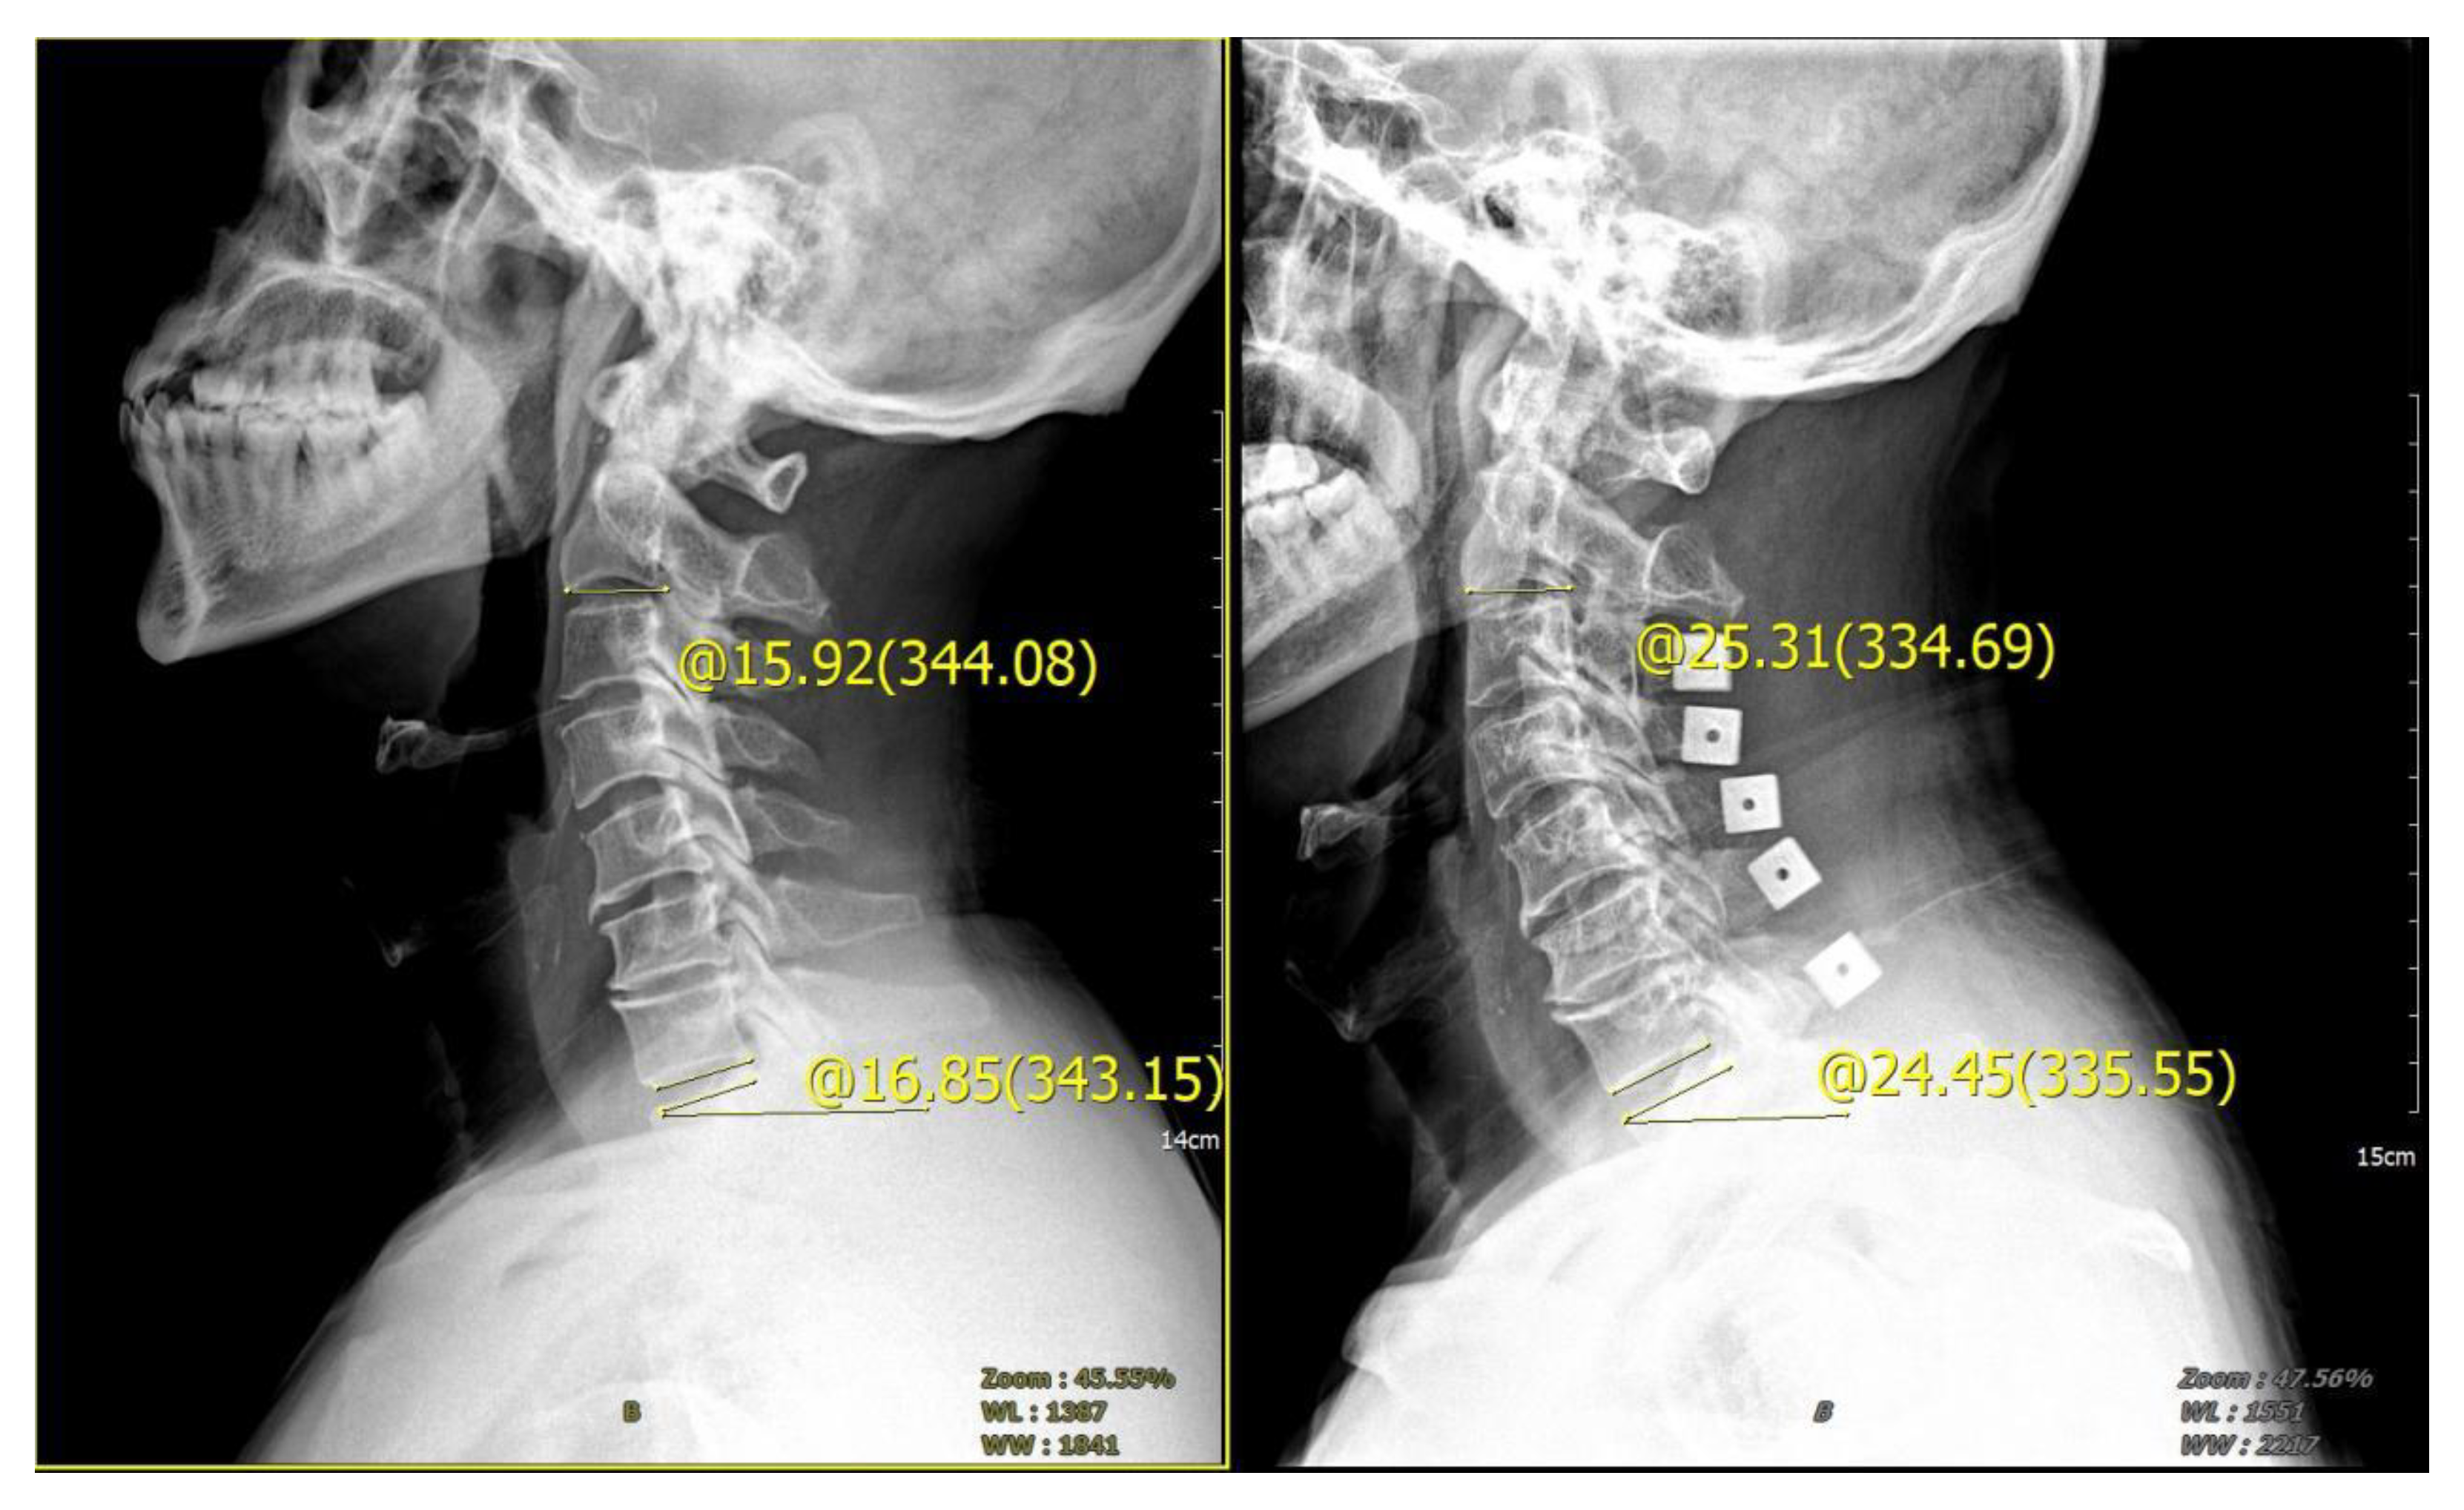

Figure 2.

Cobb angle of cervical curvature. The angle formed by the parallel line of C2 lower endplate and C7 lower endplate represents the curvature of cervical vertebra.

Figure 5.

Male, 65 years old, diagnosed with CSM, cervical vertebra 3–7 posterior double door. The preoperative tilt angle of T1 was 16.85°, the preoperative cervical curvature was 15.92°, and the postoperative follow-up 3 months later showed that the cervical curvature was 25.31°, which increased by 9.39°.